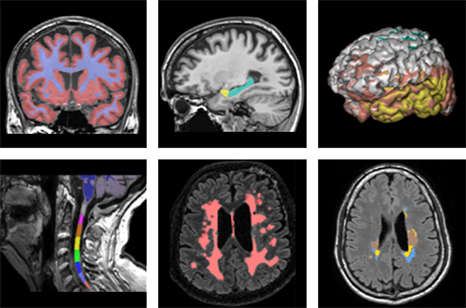

QyScore анализирует снимки МРТ для обнаружения признаков болезней мозга

Французская компания Qynapse получила официальное разрешение американских регулирующих отрасль здравоохранения органов (FDA) на использование программного обеспечения QyScore, которое анализирует сканы МРТ мозга на наличие биомаркеров заболеваний центральной нервной системы. Эта система предназначена для диагностики и мониторинга таких заболеваний, как болезнь Альцгеймера, болезнь Паркинсона и рассеянный склероз, и может использоваться для помощи врачам. Технология уже получила аналогичное разрешение регулирующих органов Евросоюза в 2017 году.

QyScore количественно оценивает продольные изменения в областях мозга, связанных с различными заболеваниями, и помогает устранить вариабельность, вызванную участием разных людей, оценивающих одни и те же изображения МРТ. Поскольку технология указывает на подозрительные биомаркеры и обеспечивает сравнение с изображениями здоровых людей, она может помочь значительно ускорить диагностику.

Отчеты о пациентах составляются через несколько минут после сканирования, и использование QyScore на клинический рабочий процесс существенно не влияет.

QyScore играет важную роль в диагностике деменции на ранней стадии заболевания, когда это сделать еще сложно. Автоматическая количественная оценка таких маркеров, как атрофия мозга, гиперчувствительность белого вещества и т.д., обеспечивает очень ценную помощь для поддержки своевременной диагностики и эффективного мониторинга прогрессирования болезни.